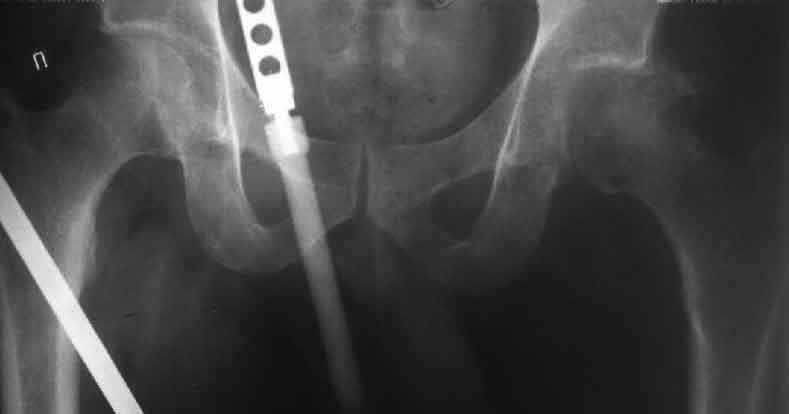

Насчет 8 см согласен с А.Н. Челноковым, это наверное ортопедическое за счет приводящей, сгибательной контрактуры и, возможно, колена. на ликвидацию укорочения у нас обычно уходит около 2-х нед. снимки в приложении, возможно не очень показательные, но других с ходу не нашел, завтра еще поищу.

Еще пара фото, ситуация несколько иная, задачи те же, открытое вправление застарелого вывиха в 2002, молодой возраст. Сейчас госпитализирована для эндопротезирования.